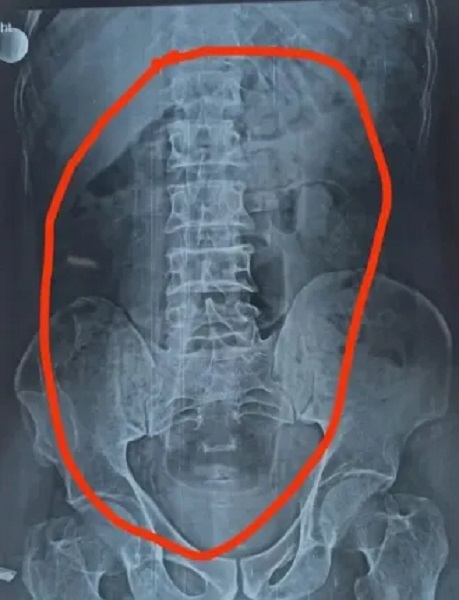

Hindistan’ın Madhya Pradesh eyaletindeki bir hastanede 55 yaşındaki bir hasta şiddetli mide ağrısı ile acile geldi.

Ağrı için röntgen isteyen doktor gördüklerine inanamadı. Çekilen röntgende adamın midesinde yabancı bir cismin bulunduğu tespit edilerek acilen ameliyata alındı.

Adamın midesindeki 20 cm büyüklüğündeki plastik şişe cerrahi operasyonla çıkartıldı. Uzman laparoskopik cerrah Manoj Chowdhary uzun saatler süren operasyonun ardından plastik şişeyi sağlam bir şekilde çıkartıldığını açıkladı.

Ameliyatın ardından gözlem altında tutulan adamın operasyonuna ilişkin olarak hasta mahremiyeti koşulları nedeniyle ayrıntılara yer verilmedi. Plastik şişenin hastanın midesinde bulunma nedeni ve yer alma şekline dair herhangi bir açıklama yapılmadı.

Doktor hastayla yaptığı görüşmesinde 55 yaşındaki adamın “Oraya nasıl geldiğini bilmiyorum” ifadelerini kullandığını söyledi. Kaynak: TGRT Haber